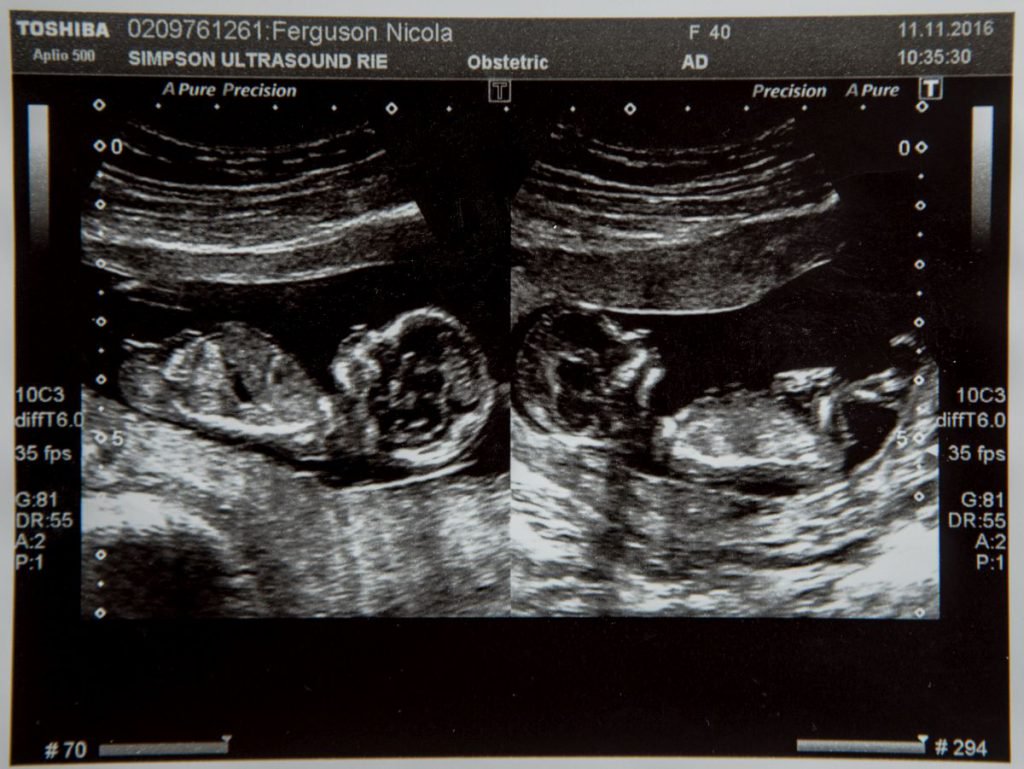

Clipe de groază pentru o femeie însărcinată cu gemene: medicii i-au spus că una dintre ele trebuie să moară! Cum a ales